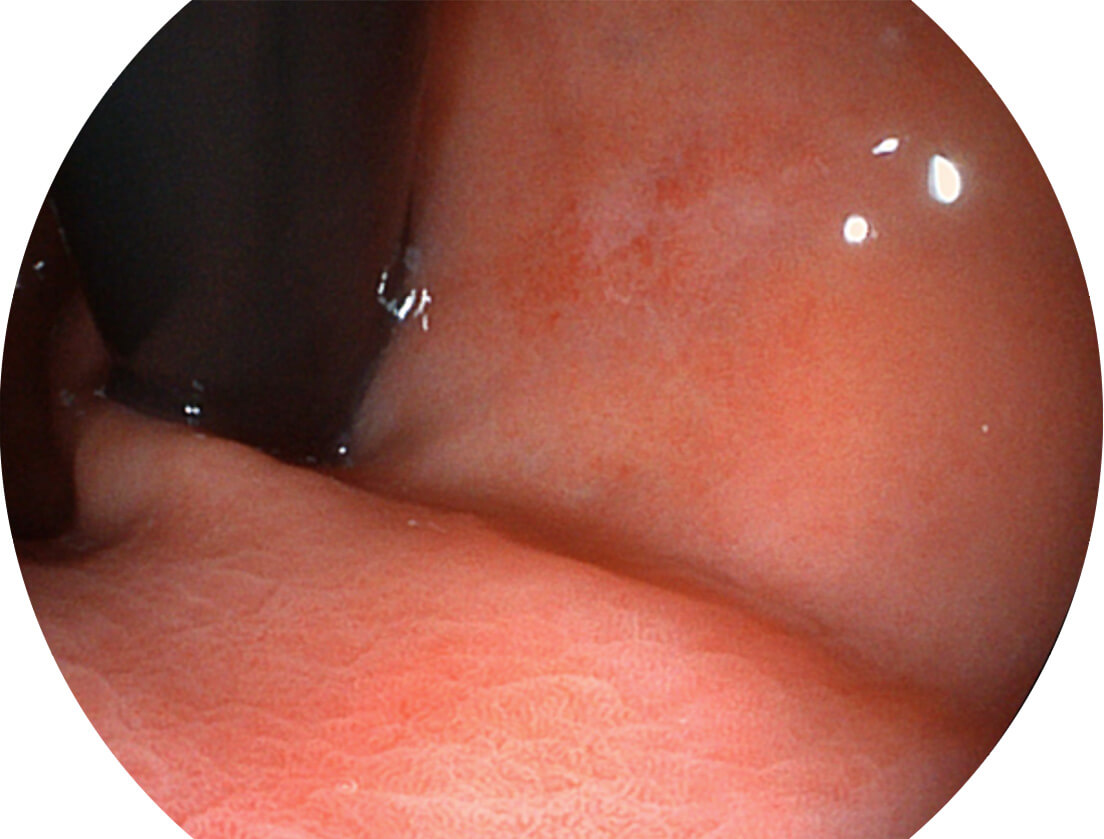

• 白光图像 VIST图像